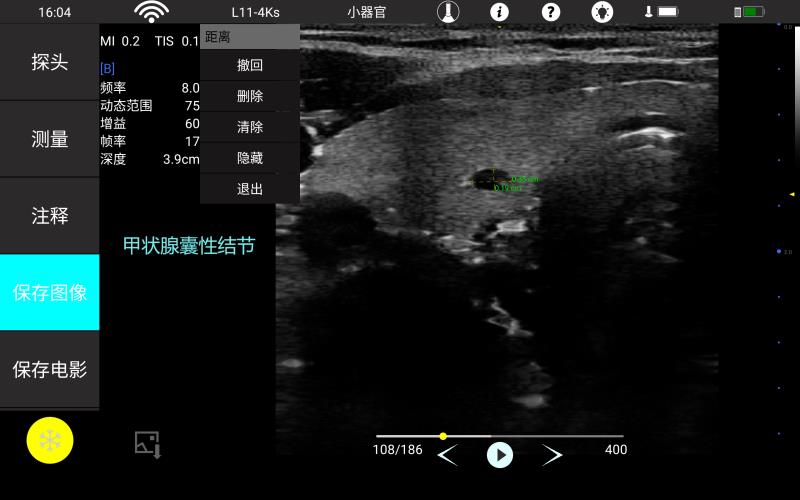

• 线阵

甲状腺

血管

神经

肌骨等